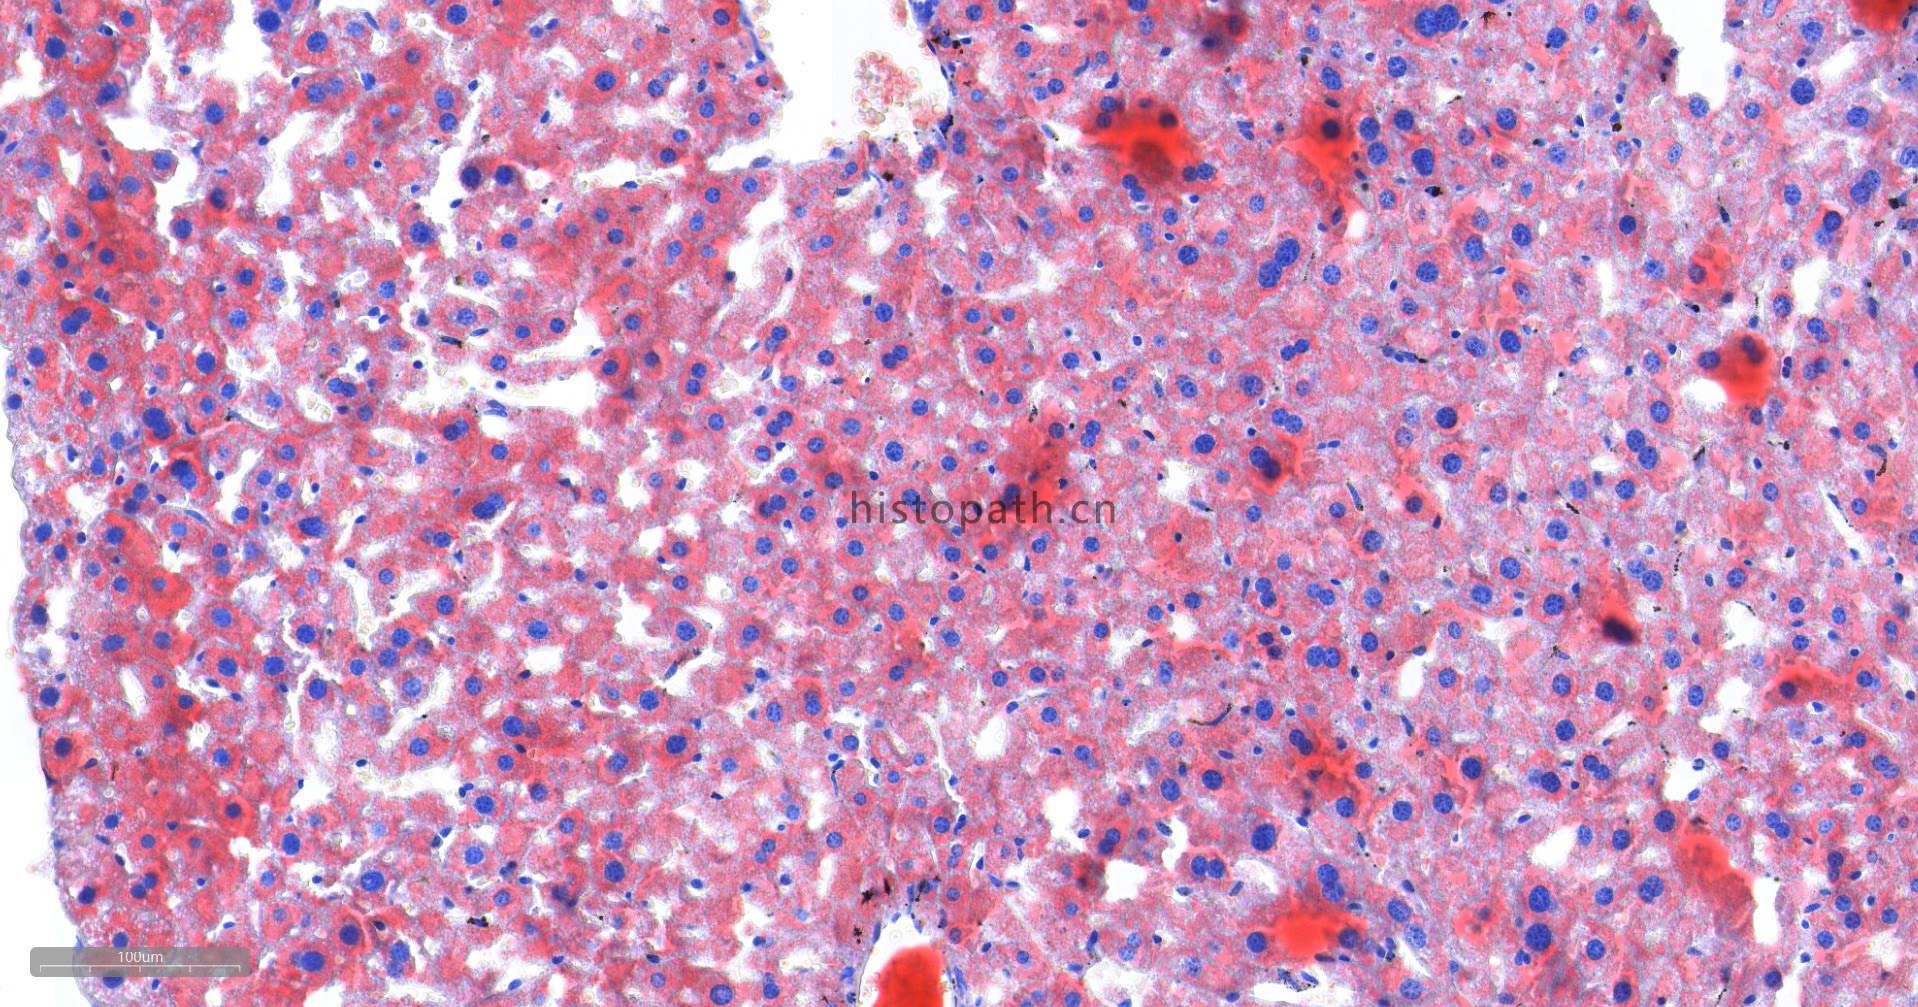

苏丹Ⅲ染色原理:

脂类包括脂肪和类脂,根据其性质可分为中性脂肪、脂肪酸、胆固醇、磷脂及其他类脂质。中性脂类包括甘油三酯、胆固醇、类固醇及糖酯等。酸性脂类包括脂肪酸和磷脂等。各种脂肪与类脂质在体内都是混合存在的。体脂主要为中性脂肪。类脂的功能为与蛋白质、糖类结合构成细胞的基本成分。脂质的共同物理性质为不溶于水而易溶于乙醇、乙醚、四氯化碳等有机溶剂,因此,选择固定剂是应避免用有机溶剂。脂质理想的固定剂是甲醛钙或10%中性缓冲福尔马林。脂肪染色切片要用冰冻切片。

染色结果分析:中性脂肪呈橙红色,细胞核呈蓝色。